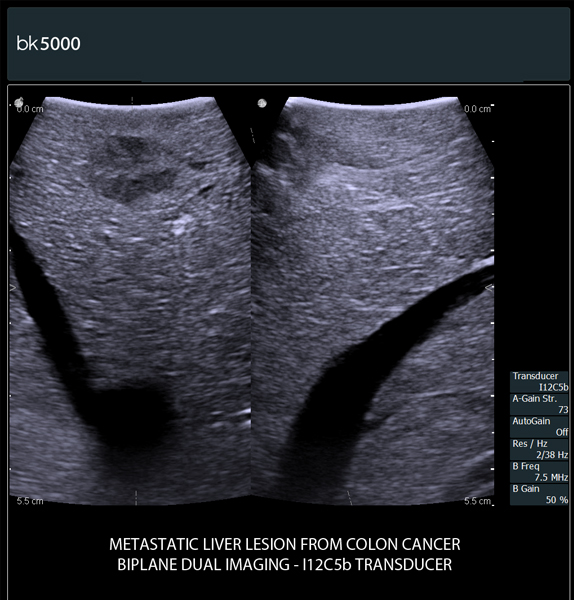

- Ngoài ứng dụng hình ảnh siêu âm chẩn đoán thông thường thì Đặc biệt được sử dụng trong phẫu thuật:

+ Điều trị Hủy u gan dưới hướng dẫn của siêu âm: Bằng sóng cao tần (RFA), Microwave ablation, sinh thiết gan, chọc hút dẫn lưu gan...